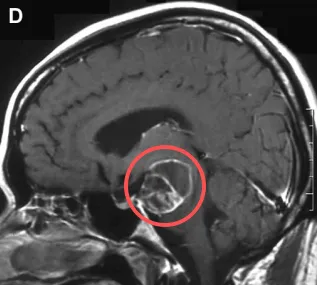

对于原发性脑干出血患者,摆在医生和家人面前的首要难题往往是:选择保守治疗,还是冒险进行手术清除血肿? 这一决策为何会异常艰难?先一起来看看70岁的她与原发性脑干出血的生死较量...